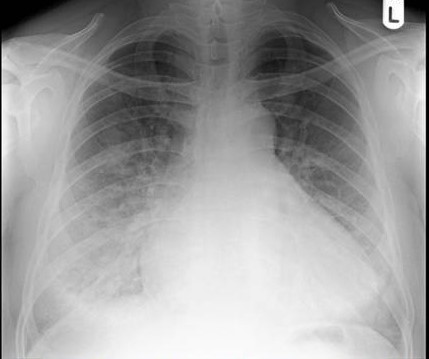

His follow up chest x-ray is shown below:

He is transferred out of the ICU, but will continue to have telemetry monitoring.